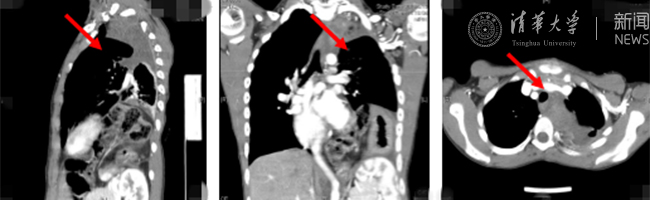

首页网8月30日电(通讯员 杨峰)如图中所示,本是正常人心脏、左肺的位置,被发于神经鞘的巨大肿瘤占据,导致一位刚满12岁的男孩胸痛、咳嗽、呼吸困难。近日,北京清华长庚医院神经外科与胸外科联手,由神经外科王贵怀主任主刀,成功为男孩切除胸腔巨大神经鞘肿瘤。

患者胸腔内巨大的肿瘤。

半年前,患者经常会出现胸痛、咳嗽和呼吸困难,在当地医院检查发现左侧胸腔巨大占位,左肺及心脏明显受压。王贵怀大夫接诊,仔细查体了解病情,并反复认真阅片后,认为左侧胸腔巨大肿瘤来自于胸椎椎管内,神经鞘瘤可能性大。该肿瘤体积巨大,占据绝大部分胸腔空间,压迫左肺、纵隔大血管及膈肌。